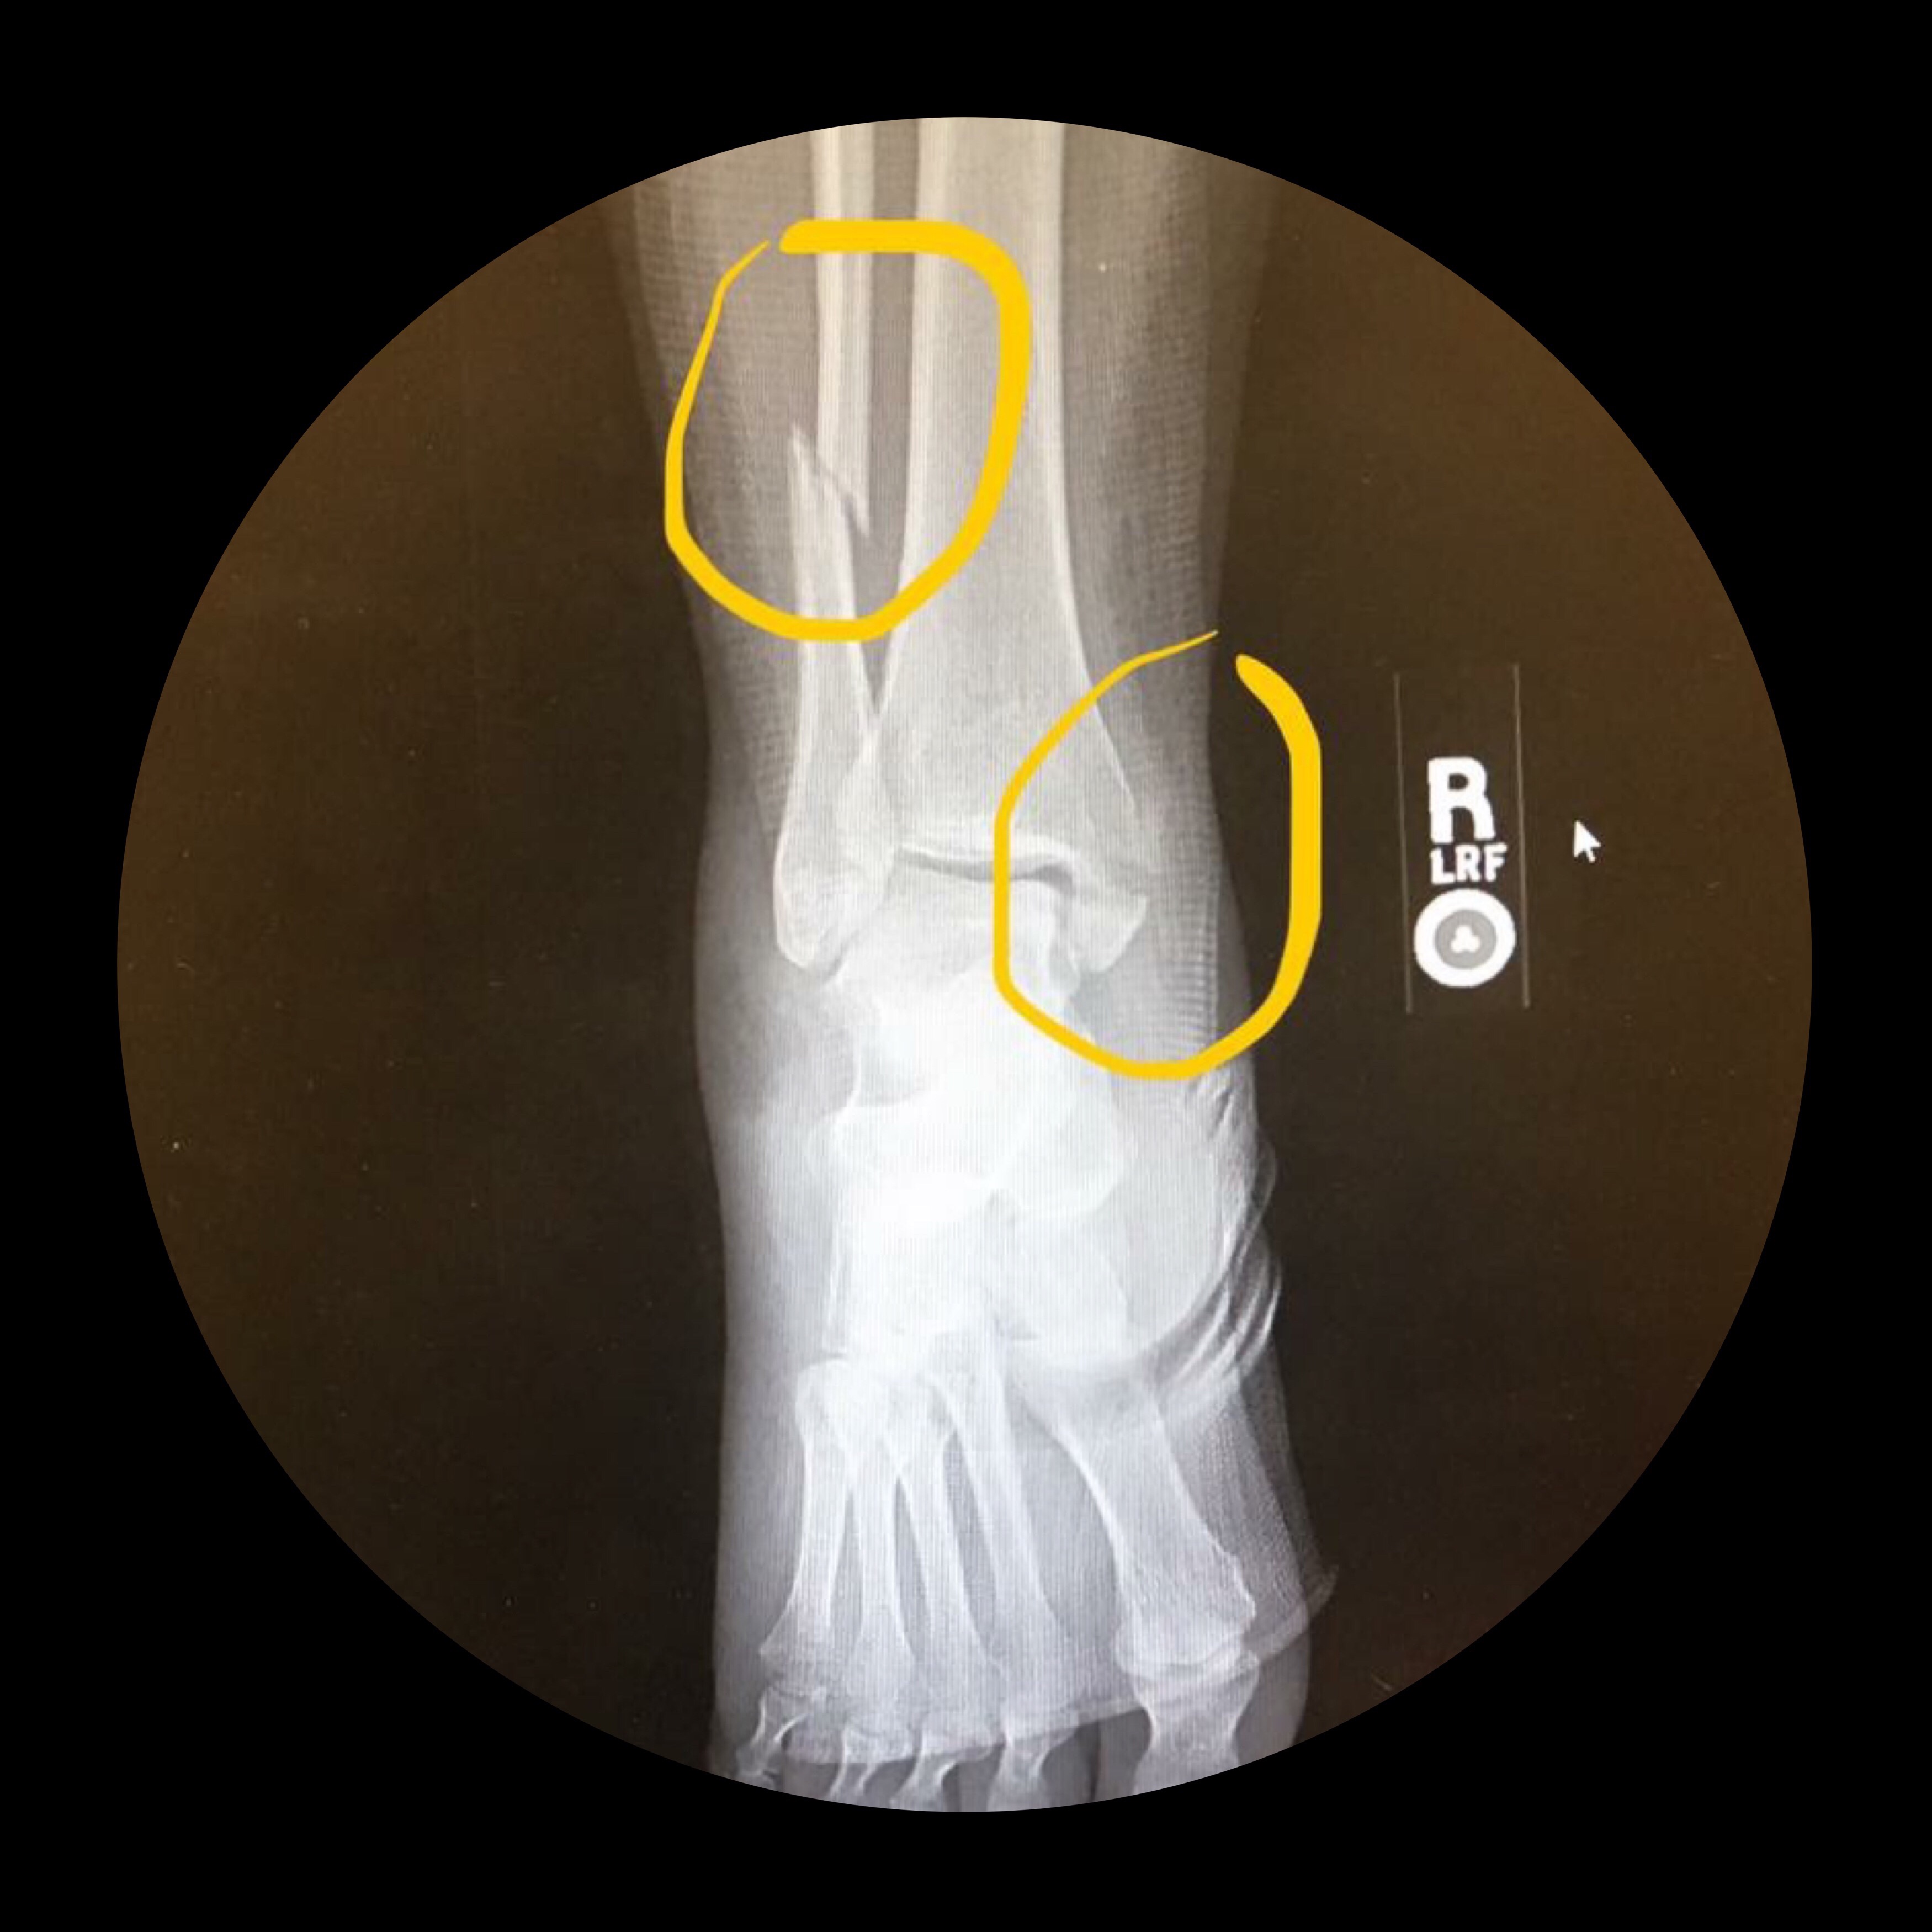

This is my broken leg. I am not sure if you can see both sides, but the x-ray reveals a broken fibula and tibia. The more visible break in the top of the photo and also my ankle. Being broken, in more ways than one, was part of a series of events that led to … Continue reading Broken